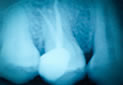

Crowns are the best way to strengthen compromised teeth, helping you to protect them from cracks and breakage and preserve them for a lifetime. Especially recommended for teeth that have required root canal treatment. A bridge is one or more false teeth that sit between crowns to replace lost teeth.

Root canal treatment is required when the nerve that is inside the root of the tooth has died or become infected. This can be triggered by past trauma or decay. It involves removing the affected nerve, applying medication and inserting a root and surface filling over approximately two visits.